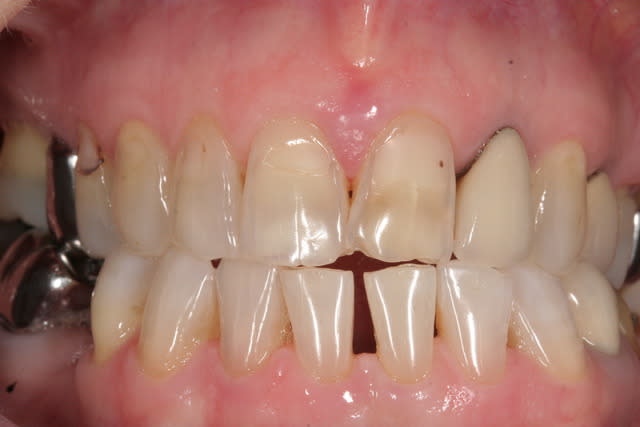

OM1. Yeah !

On passe de la teinte tétracycline la plus sombre à jacob delafont. 8 ans après patient toujours ravi. -)))

J'ai passé tout un après midi à faire ca avec prolongation en soirée et encore aidé du protho ivoclar. Plus jamais. -)

Notez l'effet maquillage encore plus blanc du plus bel effet. -)))